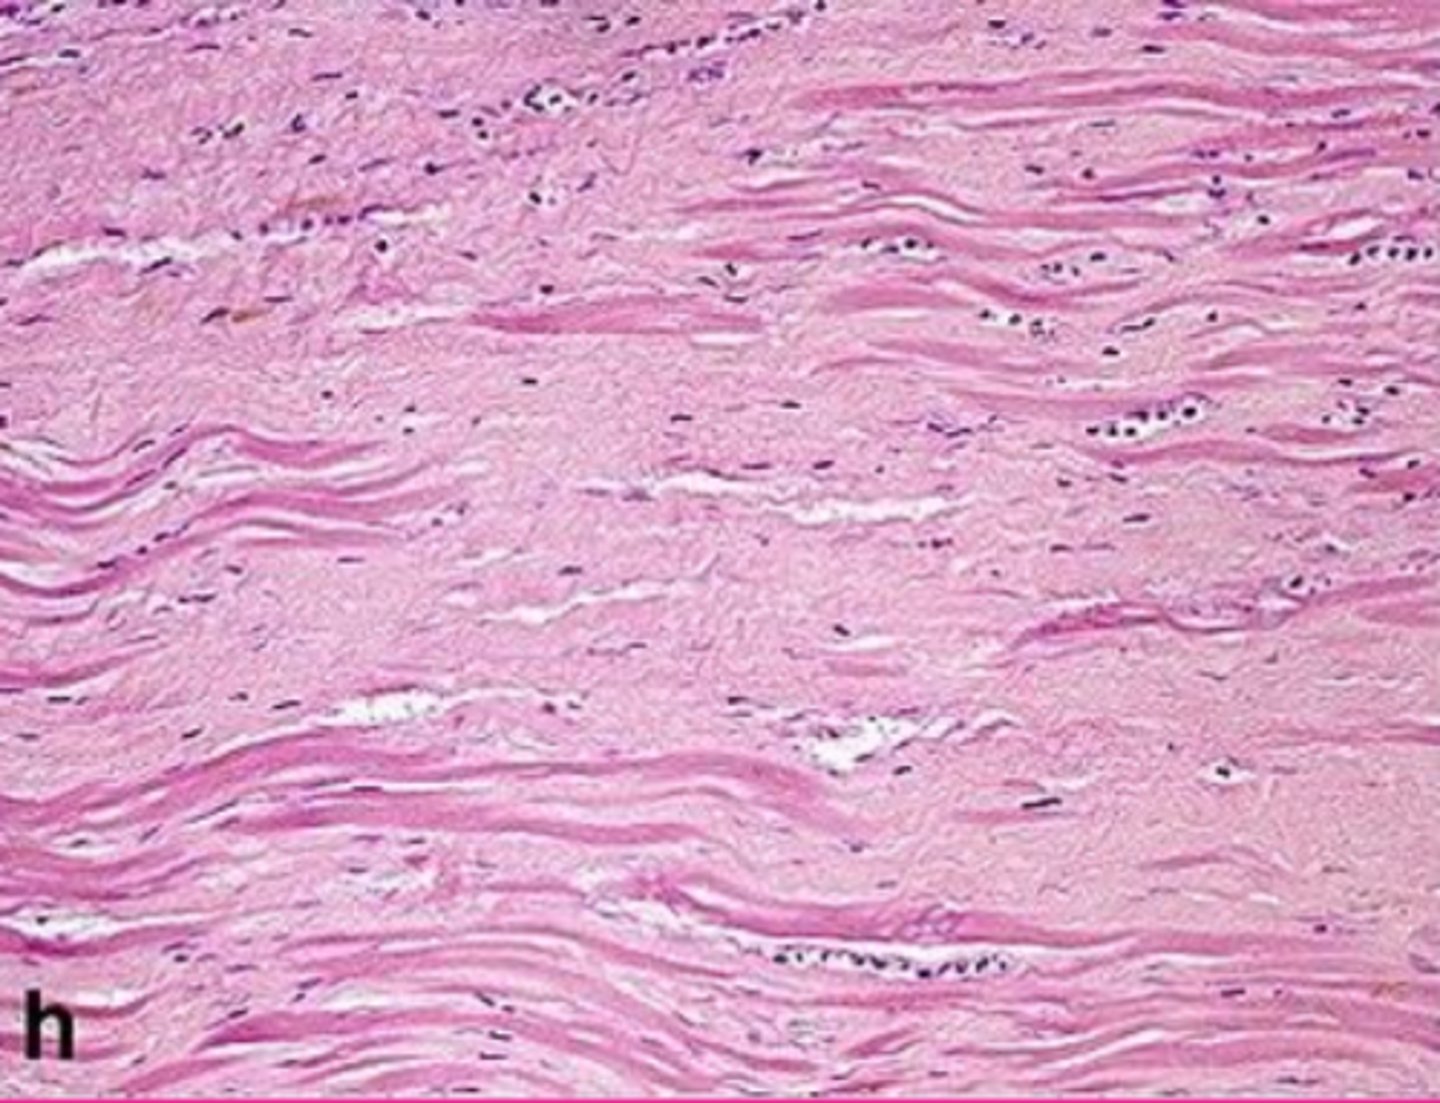

myocardial fibrosis

Describe this extracellular inclusion (heart muscle)

<p>Describe this extracellular inclusion (heart muscle)</p>